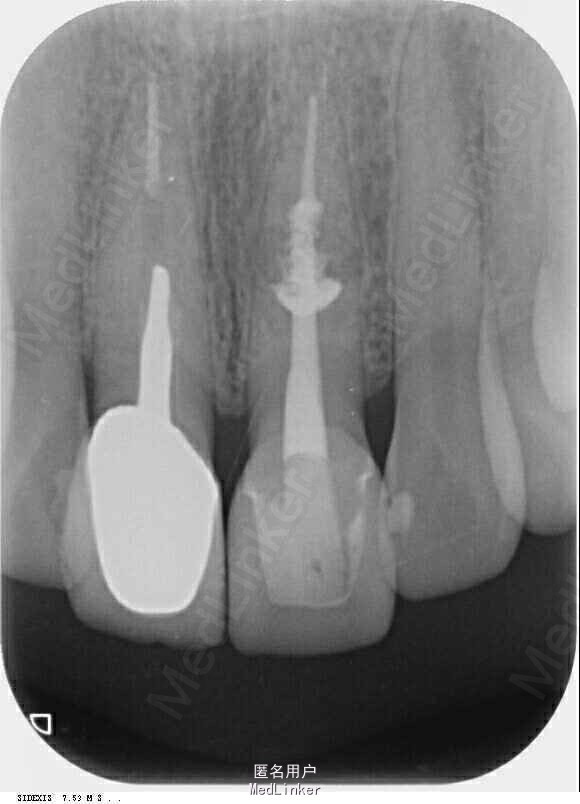

诊断:左上中切牙牙根内吸收。治疗计划:左上中切牙根管治疗,全冠修复。 治疗过程:患者知情同意。使用含1/100,000肾上腺素的4%盐酸阿替卡因(碧兰麻,艾龙)局部浸润麻醉,橡皮障隔湿。去腐未尽露髓,露髓孔出血多。开髓,使用10#不锈钢K锉(MANI,日本)探查根管,根管中段有钙化物阻挡,不能达到牙根全长(图3A)。在显微镜下(Leica M400E,莱卡, 德国) 使用超声尖(E1根管治疗超声尖,啄木鸟公司,中国)通开,采用根管长度测量仪(Root ZX, Morita公司,日本)加诊断丝片法(图1B)测量根管长22 mm。使用控制扭矩马达(X-smart,登士柏)和镍钛旋转器械(Hero 642, Micromega)根管预备,根管预备过程中使用5.25%次氯酸钠溶液冲洗。 根备完成后使用超声荡洗根管,5.25%次氯酸钠溶液3 分钟, 17% EDTA溶液1分钟。干燥根管,使用螺旋充填器根管内封氢氧化钙糊,氧化锌丁香油水门汀暂封。1周后患者复诊,患者述无术后不适,检查暂封完好,无叩痛,不松,牙龈无红肿瘘管。使用橡皮障隔湿,去除暂封物,超声荡洗根管,5.25%次氯酸钠溶液3 分钟, 17% EDTA溶液1分钟。干燥根管,牙胶尖(达雅鼎,中国)和必兰根充糊剂(Cortisomol, 艾龙公司,法国)热垂直加压法根管充填。术后片显示根充恰填,可见牙胶/糊剂被压入钙化物周围和内部缝隙内

1月后复查无不适,行全瓷冠修复。8月2周后复查,患者无不适主诉,牙冠美观,边缘完好,患牙无叩痛,不松动,牙龈无红肿瘘管, X线片示根周膜连续,根尖周未见异常。建议患者避免用前牙撕咬食物,定期复查。 讨论: 临床上,由于牙根内吸收和牙根外吸收的治疗方法和预后不同,常需要对两者进行鉴别诊断。过去通常采用偏移投照的方法鉴别两者。在偏移投照片上,外吸收病损和根管轮廓相对位置较正位片会发生变化,而内吸收病损则不会[12]。近期研究和病例报告均显示CBCT有助于牙根吸收病例的诊断[3, 6, 13]。本病例中使用CBCT判断缺损大小、内容物形状和根管壁可能侧穿孔的位置,起到了辅助诊断治疗的作用。 替代性根管内吸收的根管治疗存在一定的特殊性。吸收缺损内形成的钙化物可能会阻碍根管通畅;钙化物和根管壁形成死腔,内可藏坏死牙髓组织和细菌,如果不能彻底清创,可能会影响根管治疗的预后。本病例使用超声尖穿透钙化物;用5.25%次氯酸钠和17%EDTA溶液超声荡洗根管,以最大限度地溶解根管及死腔内的感染物质。氢氧化钙有抗菌和溶解残余坏死组织碎屑的作用[7, 14],在牙根内吸收治疗中,通常推荐使用氢氧化钙作为根管封药药物[11]。本病例采用氢氧化钙根管封药1周,和根管冲洗起协同作用,有利于更彻底的清洁根管。 因为无机三氧化物聚合物(MTA)具有良好的封闭作用和抗菌作用[15-17],有学者建议在发生侧穿的牙根内吸收病例使用其充填根管[7, 14]。但是本病例笔者考虑MTA流动性差,难以进入钙化物和根管壁之间的间隙,因而选择采用热牙胶垂直加压技术充填根管,并取得了满意的三维根管充填效果。 根管内吸收病例的治疗长期疗效存在一定不确定性。虽然文献报道有很多长期成功病例[5, 14],但是也有长期效果不佳的病例。有一例报道患牙在8年后发生了根折,因患者否认外伤,由此怀疑根折是前牙受过度咬合力所致[4].。笔者认为应建议病人避免用前牙撕咬食物,以延长患牙的寿命。本病例虽然取得了良好短期疗效,但是长期疗效尚需进一步观察。